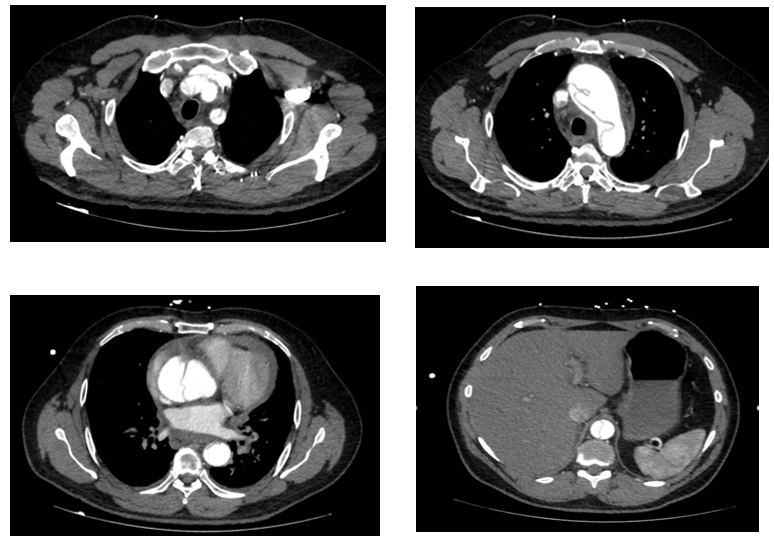

Fig 1

CT aortogram showed Stanford A thoraco-abdominal dissection with pre-existing abnormal ascending aorta. Unfortunately, shortly after returning from CT the patient deteriorated and suffered a cardiac arrest. Despite a prolonged resuscitation including an attempted pericardiocentesis, the patient did not survive.

Figure 1